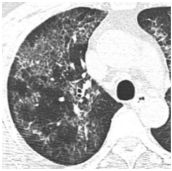

17. 50 y/o Female, Progressive dyspnea and cough for months.